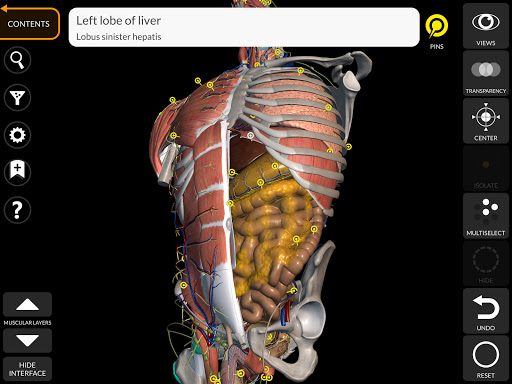

Thông qua giao diện đơn giản và trực quan, bạn có thể quan sát mọi cấu trúc giải phẫu từ mọi góc độ.

Các mô hình giải phẫu 3D đặc biệt chi tiết và có kết cấu lên đến độ phân giải 4k.

• Xoay và phóng to từng mô hình trong không gian 3D

• Bộ lọc để ẩn hoặc hiển thị từng hệ thống

• Chức năng tìm kiếm để dễ dàng tìm thấy mọi bộ phận giải phẫu

• Bằng cách chọn một mô hình hoặc một ghim, thuật ngữ giải phẫu liên quan sẽ hiển thị